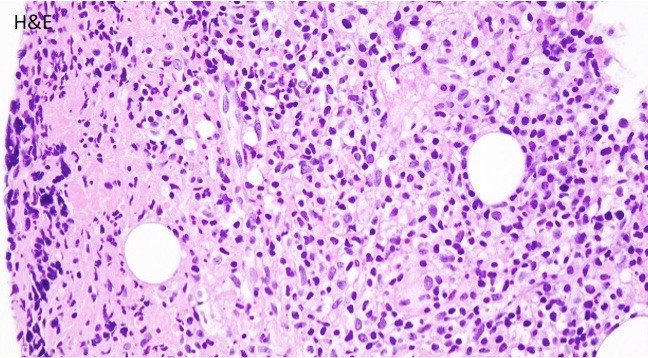

A biopsy of the bone marrow was performed.

Microscopic Findings

The bone core biopsy revealed a hypercellular marrow for the patient’s age with a pronounced lymphohistiocytic infiltrate involving 30-40% of the biopsied marrow space. Interspersed along the infiltrate were large, atypical lymphoid cells with pleomorphic nuclei and prominent nucleoli. The marrow aspirate smear reveals progressive trilineage hematopoiesis with scattered hemophagocytic histiocytes.